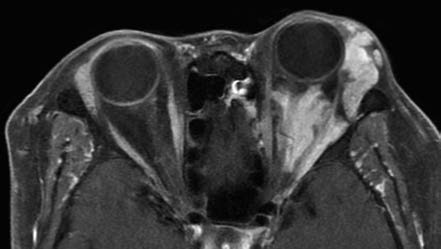

Figure 3 MRI imaging of a left orbital venous malformation

The lesion encases the optic nerve and extraocular muscles, with poorly defined boundaries and marked enhancement after contrast administration.

Expansile venous malformations exhibit pronounced eyelid swelling or proptosis during a head-down tilt test. These lesions are often poorly defined and frequently encase extraocular muscles or the optic nerve. On MRI, they present with iso- or hypointensity on T1-weighted images and iso- or hyperintensity on T2-weighted images, with marked enhancement following contrast administration.